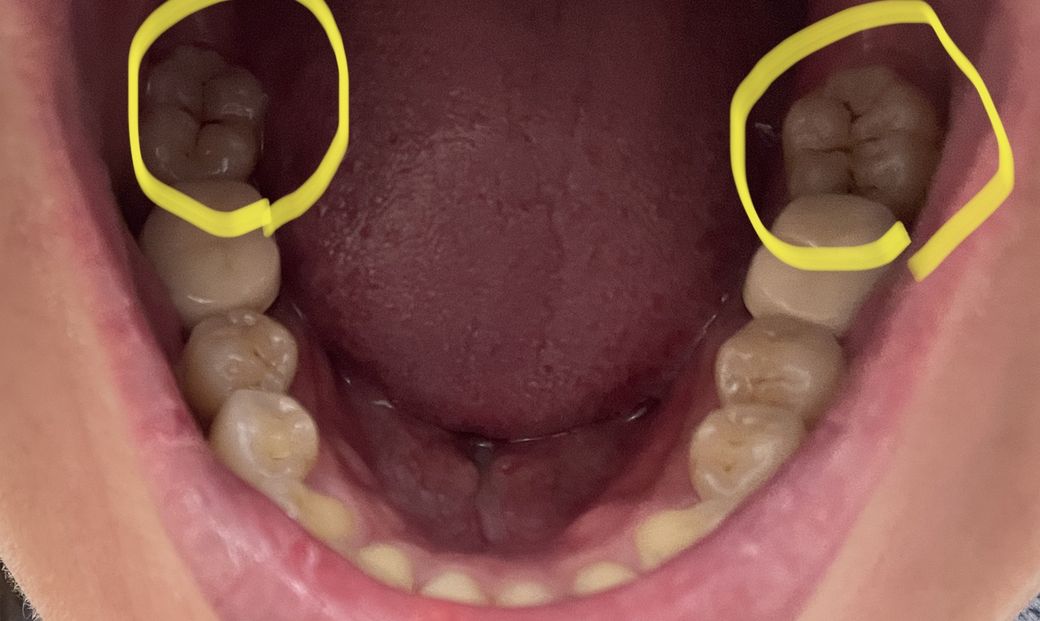

이정도 충치는 신경치료(크라운) 대상일까요? 인온레이로 치료 가능할까요?

사진첨부 죄송해요ㅠㅠ 불쾌할 수 있으나 참고하시면 될거 같습니다.

현재 아프지는 않습니다. 충치 치료는 해야 할거 같아 질의드려요~!!

사진상 오른쪽에 있는 치아의 충치는 인접면을 포함하는 충치라 인레이를 해야할 가능성이 높고,

왼쪽에 있는 치아의 충치는 인접면을 포함하지 않는 충치라 그냥 떼우는 치료를 할 수 있을 가능성이 높아보입니다.